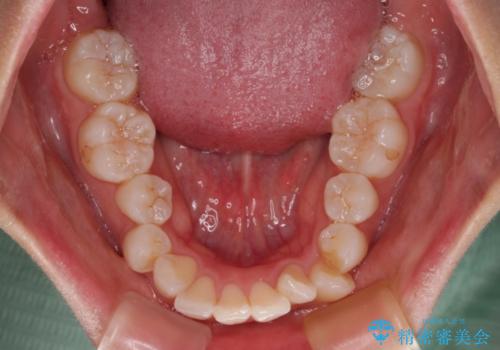

下顎はデコボコが気になっていたため、上下左右第一小臼歯4本を抜去して、ワイヤー装置にて口元の突出感を改善するよう矯正治療を行うこととしました。

下唇に前歯が当たって跡が残ってしまう状態でしたが、スッキリとした口元に仕上げることができました。